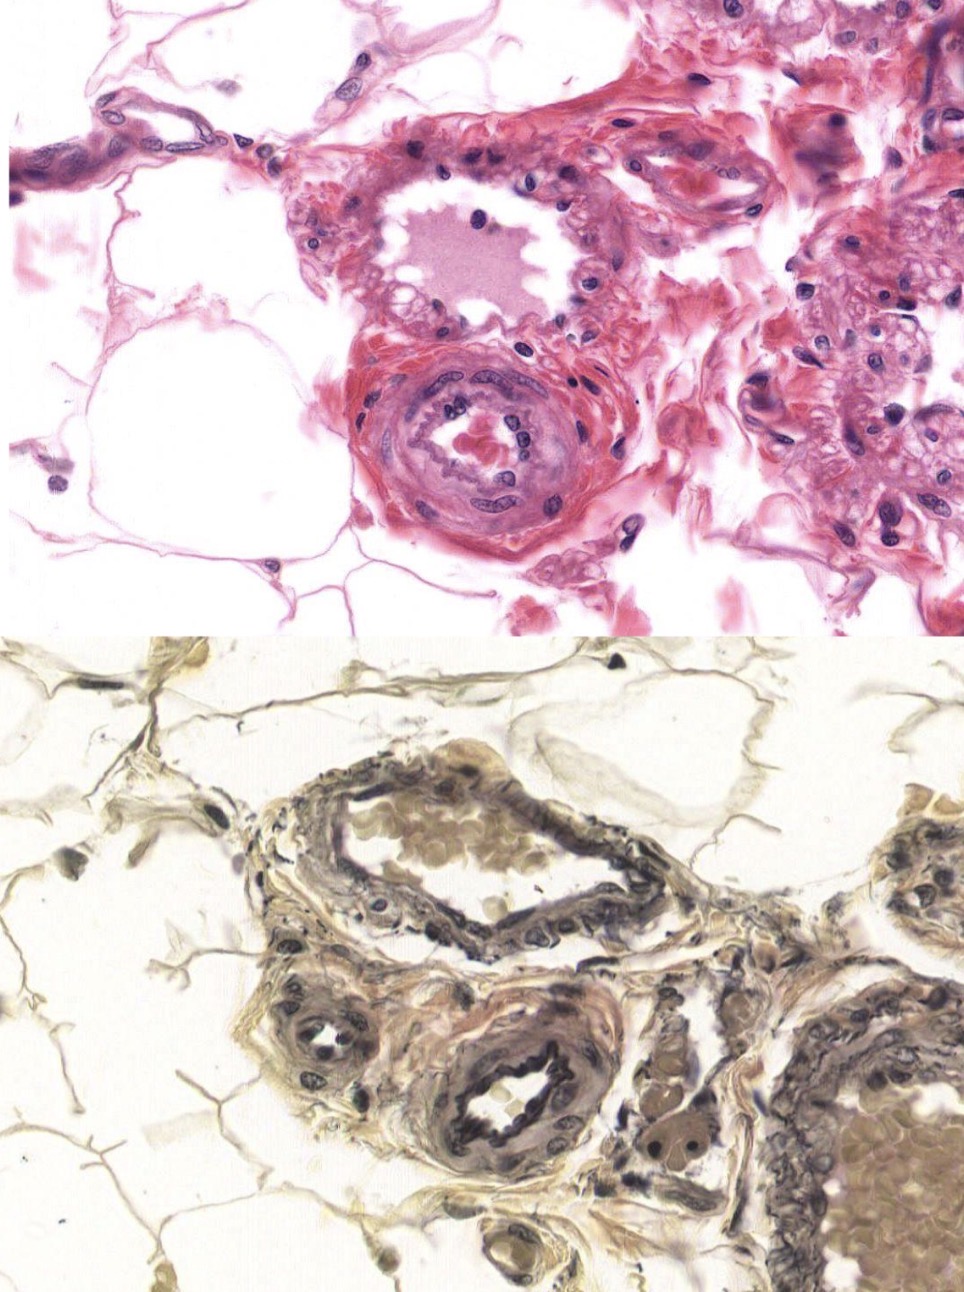

Identify the Vessel and the Layer pictured (Top and Bottom in both)

Top = Venule and Ta!

Bottom = Arteriole and Tm!